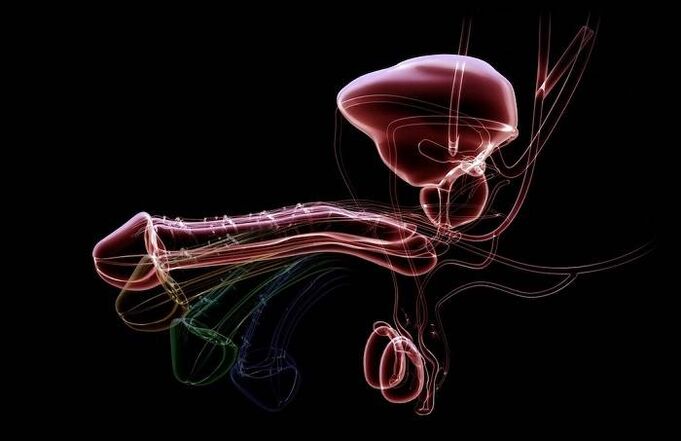

Erection is a state of excitement in the penis when a man's body is ready to have sex.The mechanism itself is due to the fact that arterial blood flows into the cavernous cavity of the penis, as a result of which the organ increases in size, changes its angle of inclination and becomes hard.

The flow during sexual arousal increases blood supply 10-20 times.

Simultaneously with the increase in blood flow, the transverse muscles of the perineum and prostate contract, as well as the muscles that compress the base of the penis.

During erection, the penis increases in volume 3-4 times and reaches a length of 14-18 cm, which is regulated by the nerve centers of the brain and lower part of the spinal cord.